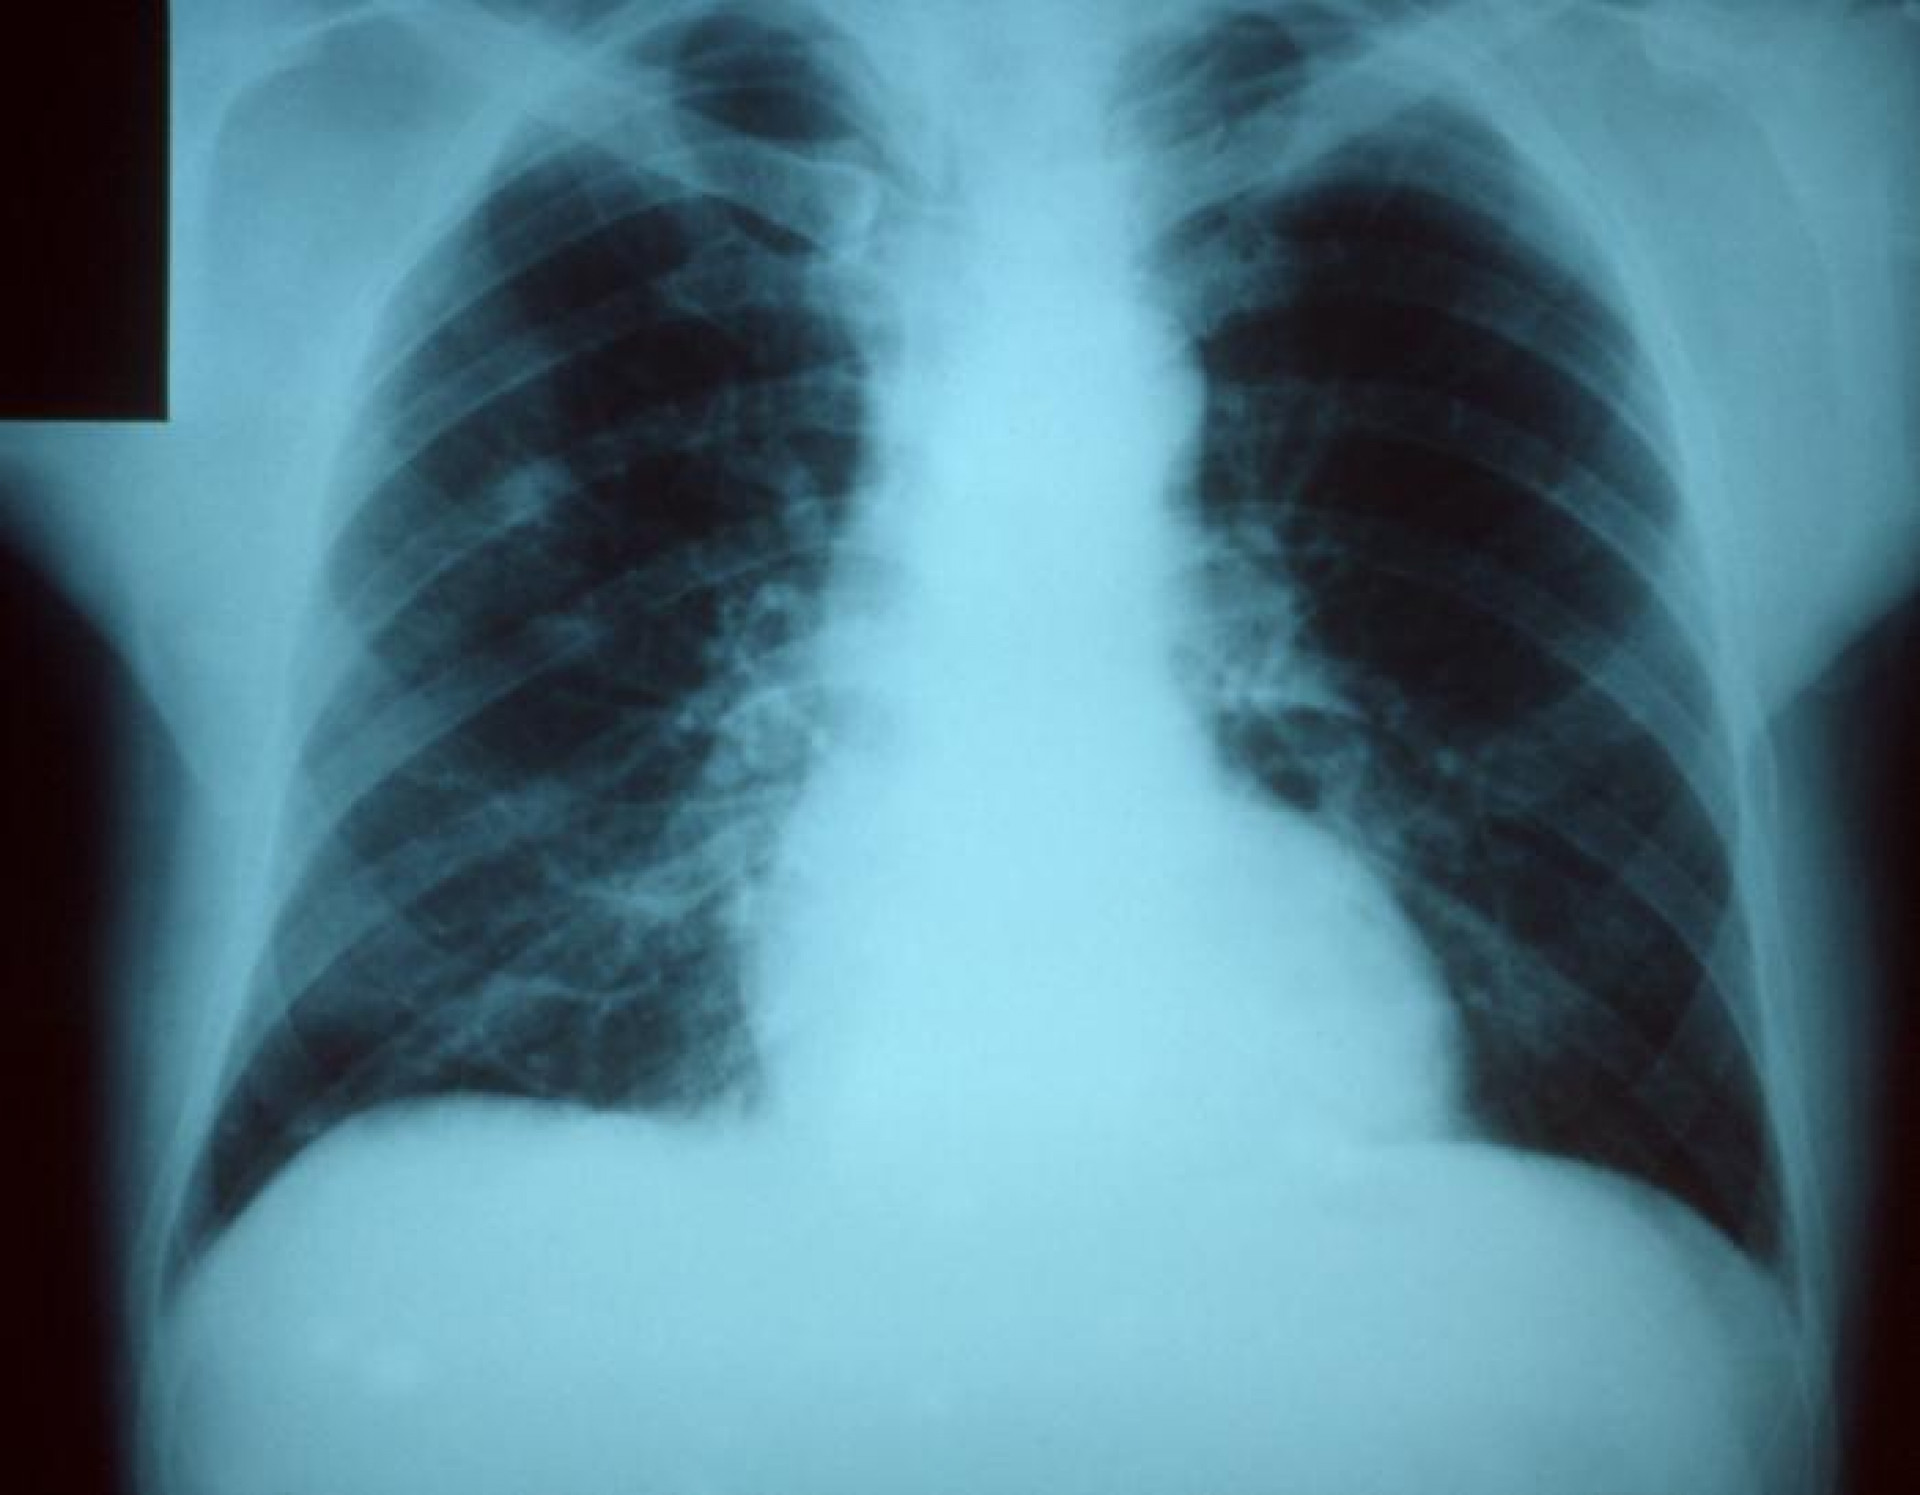

Пневмония бледность

Пневмония бледность 118 фотографий